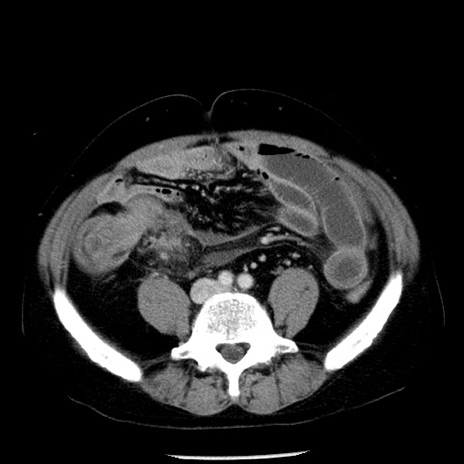

冠状断像

【症例】40歳代男性

【現病歴】2日前から胃痛あり。徐々に周期的な激痛に変化した。本日になっても激痛があるため受診。

【身体所見】意識清明、BT 38-39℃台あり、腹部:膨満、やや硬、右下腹部に圧痛あり。

【データ】WBC 8500、CRP 23.26